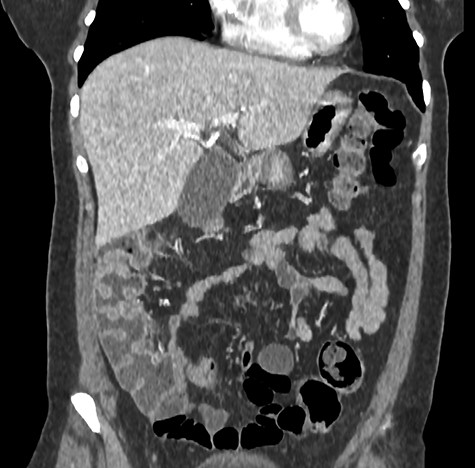

A 44-year-old female patient, without prior abdominal surgery, was admitted to the emergency department with an acute epigastric abdominal pain, without nausea. She presented similar episodes of pain in the past, without having ever requested a medical opinion. Physical examination revealed an acute epigastric pain without signs of peritonitis. Laboratory analyses were within normal limits. A computed tomography showed an internal hernia of the colon in the lesser sac, going back from the liver pedicle (Fig. 1). There were neither occlusion nor ischemia. We performed immediately a diagnostic laparoscopy with one 11-mm umbilical port and two 5-mm ports (one in the left lumbar and one in the hypogastrium). Exploration confirmed that the ascending colon and the right colonic flexure had herniated through the foramen of Winslow (Fig. 2). The colon was reduced with an atraumatic Johann’s graspers and was viable, cecum, ascending colon and the right colonic flexure was mobile due to a misapposition of the right Told fascia. To prevent recurrent herniation we performed the fixation to the lateral wall of the cecum, ascending colon and right colonic flexure with several non-absorbable sutures (Fig. 3). We did not perform the closure of the Winslow’s hiatus. Postoperatively, the patient recovery was uneventful and was discharged home 2 days later. A computed tomography was performed 1 month later for another reason, showing a good result of the right colon fixation on the lateral wall (Fig. 4). Twenty months after surgery, the patient totally recovered and has not experienced any recurrence or occlusion.

Laparoscopic exploration confirmed that the ascending colon and the right colonic flexure had herniated through the foramen of Winslow. Legend: AC: ascending colon, GB: gallbladder, LP: liver pedicle, S: stomach, TC: transverse colon.